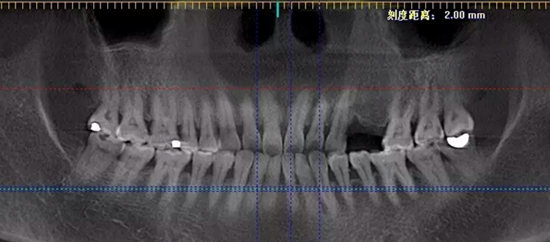

很多口腔诊所和医院开展种植牙时,了解口腔、面部颌骨情况时的依据仅仅是一张二维平面X光片,医生凭感觉和经验来设计方案实施手术,其实这样是存在一定风险的。而在麦芽口腔,一切治疗都基于口腔3维立体成像,360全方位的了解到颅面部、口腔的情况,避免手术损伤,确保植入成功,为种植牙技术系上了一条保险带。